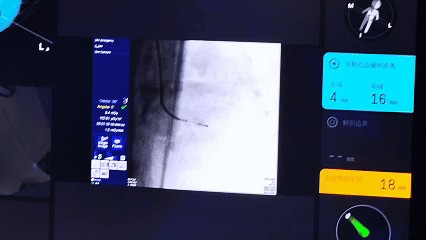

3 確認消融: 利用機器人系統(tǒng)的實時影像與定位功能,確認導管位置與病灶關系。

3 啟動治療: 在統(tǒng)一的操作視野下,一鍵啟動微波消融,并可結(jié)合影像進行實時效果評估。